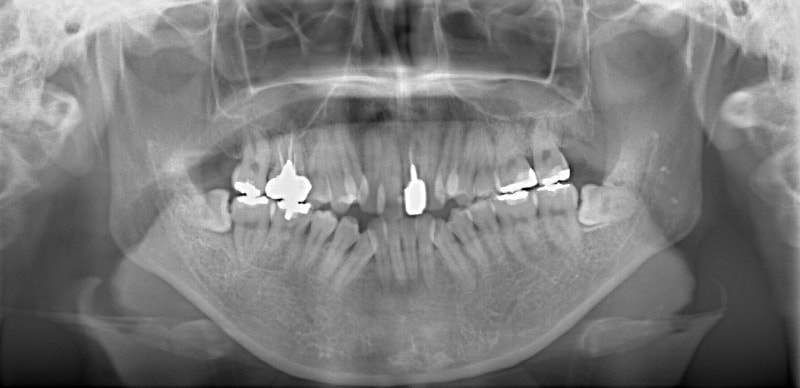

修復歯、補綴歯もあります。下顎8番が水平埋伏しています。

歯根のパラレリング(平行性)が獲得されております。

下顎8番は、両側抜歯済みです。